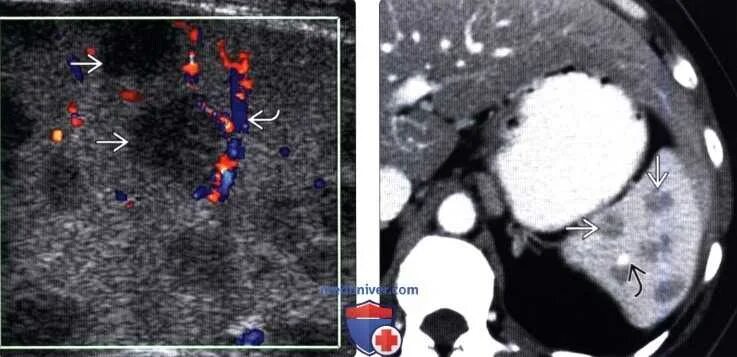

Лучевая терапия метастазов в лимфоузлах